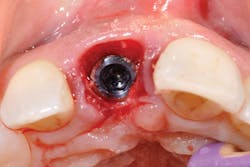

Figure 4: Implant was placed.

Extractions are a horrifying concept, yet in actuality there is pressure but no pain. Tooth No. 8, as predicted, shattered with the first touch (see Figure 3). The sound was terrible, a super loud snap. It took a moment for me to regroup, take a breath, and literally grieve the loss of my front tooth. It sounds ridiculous, but for me this was my true moment of loss, and then beginning. The prosthodontist decided that we would prepare each tooth individually, from start to finish. One tooth out, lots of drilling to remove the root, then synthetic bone-graft material mixed with my own bone (see Figure 4). As it happens, I was offered bovine bone, treated cow bone. As a nonmeat eater, there was not a chance I could handle that in addition to losing my two front teeth! Choosing synthetic was a personal option for me. Let your patients know there are cow, pig, cadaver, and synthetic materials available; it is a personal choice (see Figure 5).